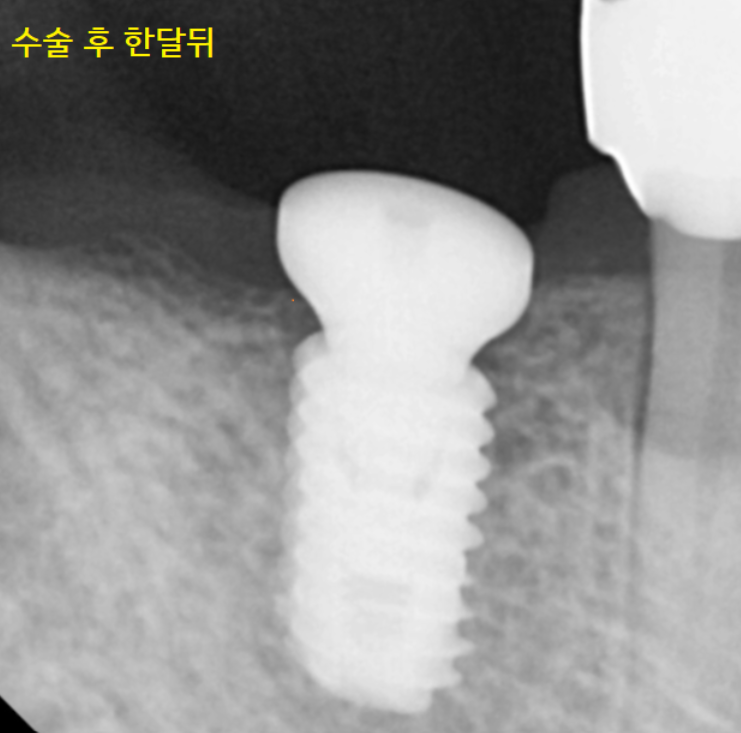

임플란트 수술 후 한 달 뒤 사진입니다.

아래 임플란트의 경우 평균적으로 3개월 정도의

임플란트와 내 뼈가 붙는 시간이 필요합니다.

아직은 임플란트 주변으로

부분 부분 어둡게 보이죠~

그렇다면 3개월 뒤의 사진을 보겠습니다.